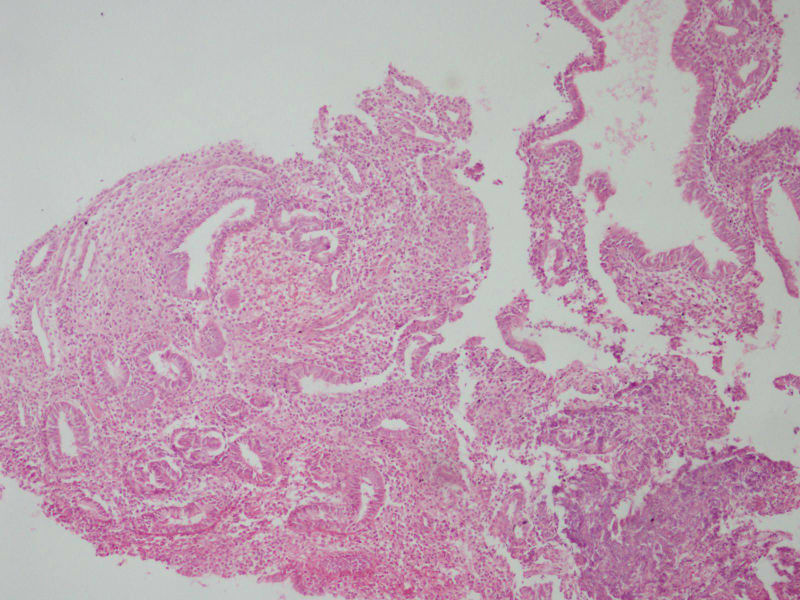

27结婚2年未避孕未怀孕停经4

染色偏红,感觉还是增值期子宫内膜。

增殖期宫内膜慢性炎症

增生期子宫内膜